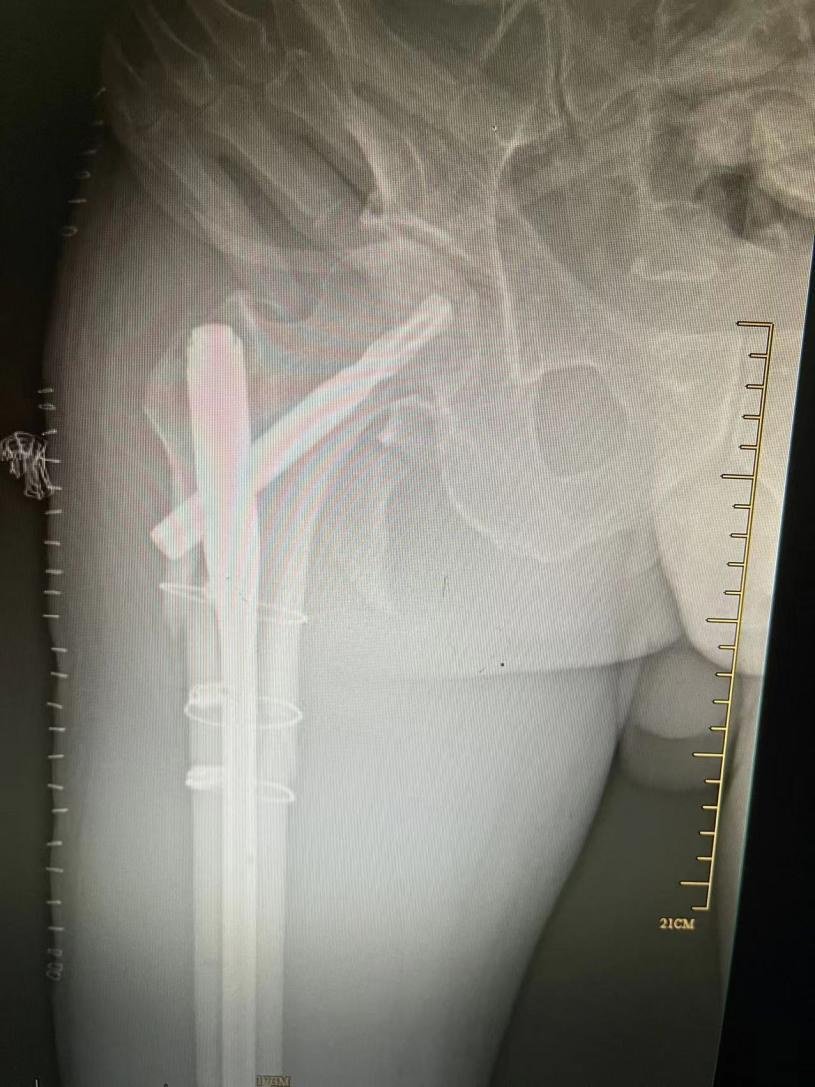

病例介紹 居住在椒江區(qū)的陳大爺70多歲了,患有帕金森綜合征20多年,慢性肺部感染約10年。一年前,陳大爺不慎跌倒導致右股骨粉碎性骨折,入住臺州市中醫(yī)院骨傷科。 病案分析 接診醫(yī)生我院骨傷科副主任中醫(yī)師徐榮敏認為,此類股骨上端骨折的病人最好的治療方案是手術。 如果保守治療,眾多并發(fā)癥是導致患者近期死亡的主要因素,雖然骨科手術并不是太難,但是患者平時2至4小時就需要服用抗帕金森藥物和吸痰,平時主要靠兒子照顧,藥效一過,痰就咳不出,全身抖動厲害。麻醉、手術、護理也各有難度,疊加起來就是難上加難,手術風險較大。 選擇手術還是保守治療,需要患者及其家屬做出選擇。 抉擇過程 在得知手術風險時,患者及其家屬也有過遲疑,考慮是否轉上級醫(yī)院治療。 但李大爺慶幸了自己的第一次抉擇,李大爺說自己幾年前在別家醫(yī)院ICU宣告治療無效回家后,后來到臺州市中醫(yī)院呼吸科才治療好的! 這次面臨著第二次抉擇,大爺還是相信臺州市中醫(yī)院!選擇手術! 手術經過 經過呼吸科、神經內科、心內科、手術室、麻醉科、ICU等科室的聯(lián)合會診,骨傷科徐榮敏醫(yī)師、陳國軍醫(yī)師等制定了詳細的手術計劃,麻醉科主任聶運明、麻醉醫(yī)生王曉等在術前也制定了詳細的麻醉計劃和應急準備,包括麻醉藥物控制劑量、術中鼻飼給予抗帕金森綜合征的藥物等。 幸運地是,手術在2小時之內順利完成,術后ICU密切觀察,第二天即回骨傷科病房。 術后護理 在常規(guī)中西醫(yī)結合治療的同時,護士長蘇韓、責任護士錢淼淼等護理同仁為其制定了細致周詳的護理計劃。在拍背、吸痰、功能鍛練等常規(guī)護理基礎上,運用辨證施護原則,因人因病而異,綜合運用耳穴埋豆、腕踝針、穴位貼敷、隔物灸等中醫(yī)適宜技術,避免了壓力性損傷、下肢深靜脈血栓、肺栓塞等并發(fā)癥的發(fā)生,安全的度過了圍手術期。 幾天后考慮患者平時患有慢性肺部感染,予轉入呼吸科。經過約1月的治療護理,李大爺恢復良好后出院! 一年后大爺的骨折愈合良好。 據徐榮敏醫(yī)師介紹,在骨傷科像這樣的老年病人其實有很多,患者往往有高血壓、糖尿病、冠心病、腦梗死、帕金森綜合征、慢性阻塞性肺疾病、腎功能不全等基礎疾病。骨傷科作為浙江省“十三五”中醫(yī)藥重點學科,設有重點學科研究室,對治療老年骨傷科疾病有獨特的研究和良好的效果。 脊柱創(chuàng)傷骨傷科為浙江省中醫(yī)重點??啤⑴_州市重點學科、上海中醫(yī)藥大學“石筱山傷科”聯(lián)盟單位。 學科特色:繼承傳統(tǒng)中醫(yī)骨傷特色治療理念,與時俱進,不斷吸收國內外當代先進骨科治療技術,中西醫(yī)結合,注重微創(chuàng),安全有效,精心護理,快速康復。 診療專長:四肢骨折脫位的手法復位加夾板(石膏)固定或手術治療;脊柱骨折的切開復位內固定;骨質疏松癥、風濕骨病、脊柱腰腿痛、骨關節(jié)炎的中西醫(yī)結合特色治療;軟組織疾患的針刀和體外沖擊波治療,骨質疏松性脊柱骨折的骨水泥成形術;頸腰椎間盤突出癥、椎管狹窄癥的椎間孔鏡手術和椎間融合手術,肩髖膝人工關節(jié)置換術,肩膝關節(jié)疾病的關節(jié)鏡手術,穴位貼敷等中醫(yī)特色治療護理技術,老年病人術后快速康復。 人才隊伍 :高級職稱5人,碩士研究生4人,多人擔任國家與省市級學會委員、副主委,主持市廳級課題多項,撰寫論文幾十篇,學術專著多部。 科室理念:中西結合,發(fā)揮特色,無痛少痛,快速康復。 聯(lián)系電話:0576-88825725